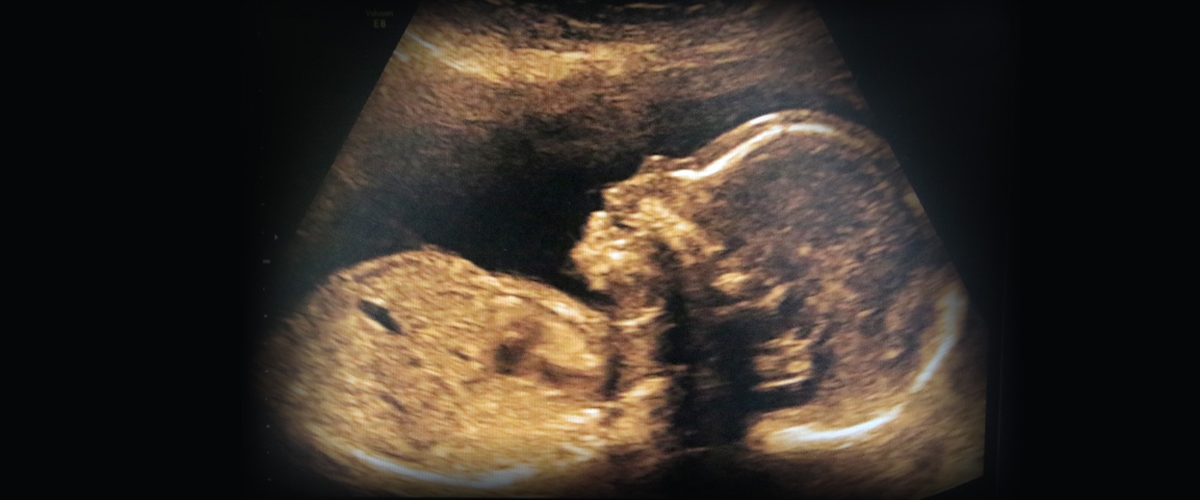

„Najednou jsem ležel na zádech, cítil jsem jakoby mravenčení v nohou, ale už jsem s nimi nehýbal. Nevěděl jsem, co se děje. Podíval jsem se doleva a říkám mu: ‚Něco se mi stalo.‘ A on na to: ‚Jo, já jsem tě střelil.‘ ‚Ty ses zbláznil,‘ povídám. V tu chvíli už stál u mě, mířil na mě a řekl: ‚Ty už mě srát nebudeš.‘ V tu chvíli mi došlo, že mě chce zabít," líčí okamžiky, kdy se i přes své zranění začal o pušku s útočníkem přetahovat. Z kapsy mu vypadl mobil. Ve chvilce nepozornosti útočníka zavolal na linku 112 a malorážku zalehl. Když se chýlilo k další potyčce, už byla policie na místě a s ní i záchranářský vrtulník, který postřeleného Josefa přepravil do královéhradecké nemocnice, kde byl operovaný. Po převozu do Liberce lékaři na spinální jednotce potvrdili, že Josef musí počítat s životem stráveným na invalidním vozíku.